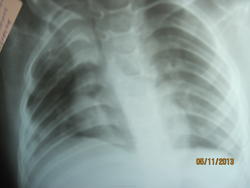

Ребенок находиться в ОРИТ. ДЦП. Диагноз ОРЗ, фарингит. С целью исключения пневмонии направлен на рентген.

Cредостение на месте. Написала инфильтрация S1, 2, 3, 5 Пневмония без динамики. Завтра снова хотят контроль делать и рентгена и УЗИ.

аспирация не исключена